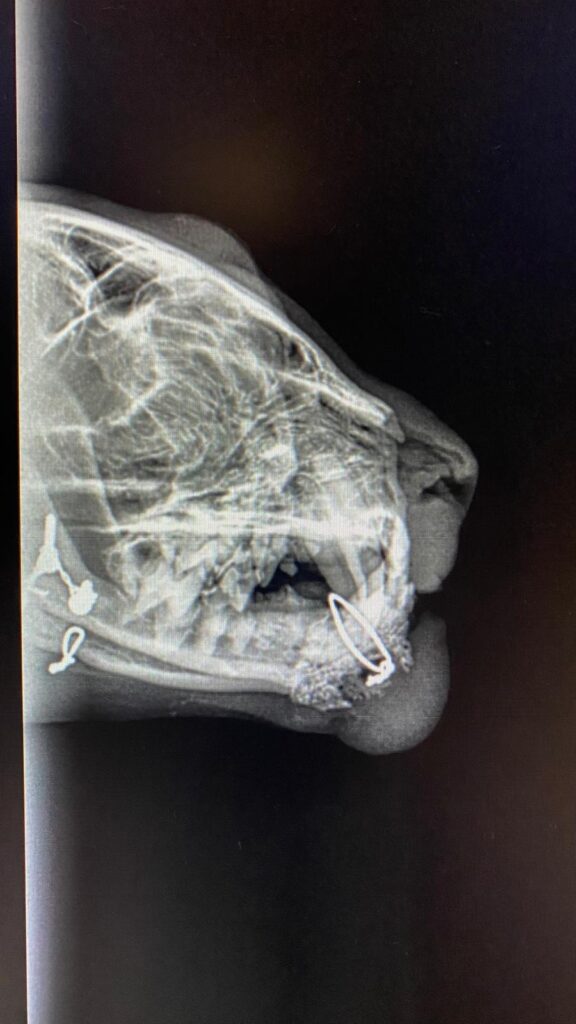

Dann der Schreck für Alle auf dem Röntgenbild:

Hubsis Unterkiefer ist wohl nach einem Bruch in der Vergangenheit verdrahtet worden, die Drähte und Schrauben sind deutlich zu erkennen! ![]()

Eine Drahtschlinge reicht bis an sein Kinn.

Es wird nun angenommen, dass diese Schlinge Hubsis Körper massiv ärgert und stört und deshalb auch diese Beule entstanden ist.